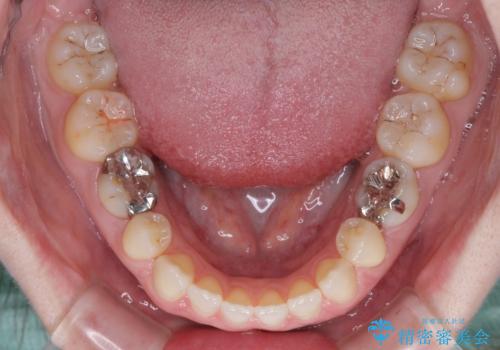

すきっ歯をインビザラインできれいな歯並びに改善

- 前歯の隙間を気にして来院された患者様です。

隙間や叢生の程度はそれほど著しいものではなかったので、インビザラインでもワイヤー矯正でも対応可能でしたが、極力目立たない装置を希望されたため、インビザラインにて矯正治療を行うこととしました。

すきっ歯の原因は色々ありますが、嚥下や発音時の舌突出癖が大きな原因となることがあります。

こちらの患者様も強い突出癖があったため、舌のトレーニング指導を行いました。